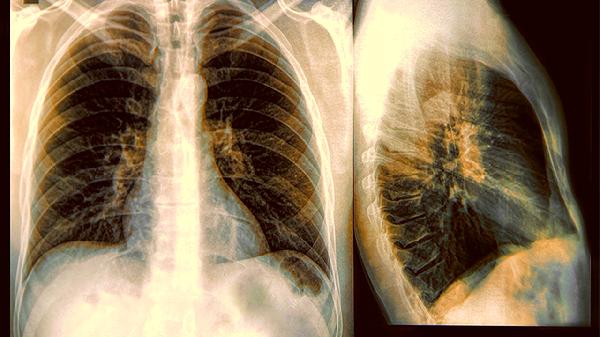

1.最容易被忽略的三个肺部异常指标

1.肺结节

小于一厘米的结节像个害羞的小朋友藏在报告尾部。虽然绝大多数是良性的小淘气,但某些特殊形状的可能需要定期观察。想象它们是肺部的小雀斑,大部分无害,少数需要更多关注。

2.轻度肺纹理增粗

这个专业术语听起来像是肺部画了素描。实际上这可能暗示早期慢性炎症或者其他变化,别忙着忽视这个"艺术创作"。

3.胸膜增厚

胸膜像肺部的外套,轻微的褶皱可能只是过去的小摩擦留下的痕迹,但也可能是某些变化的开始。